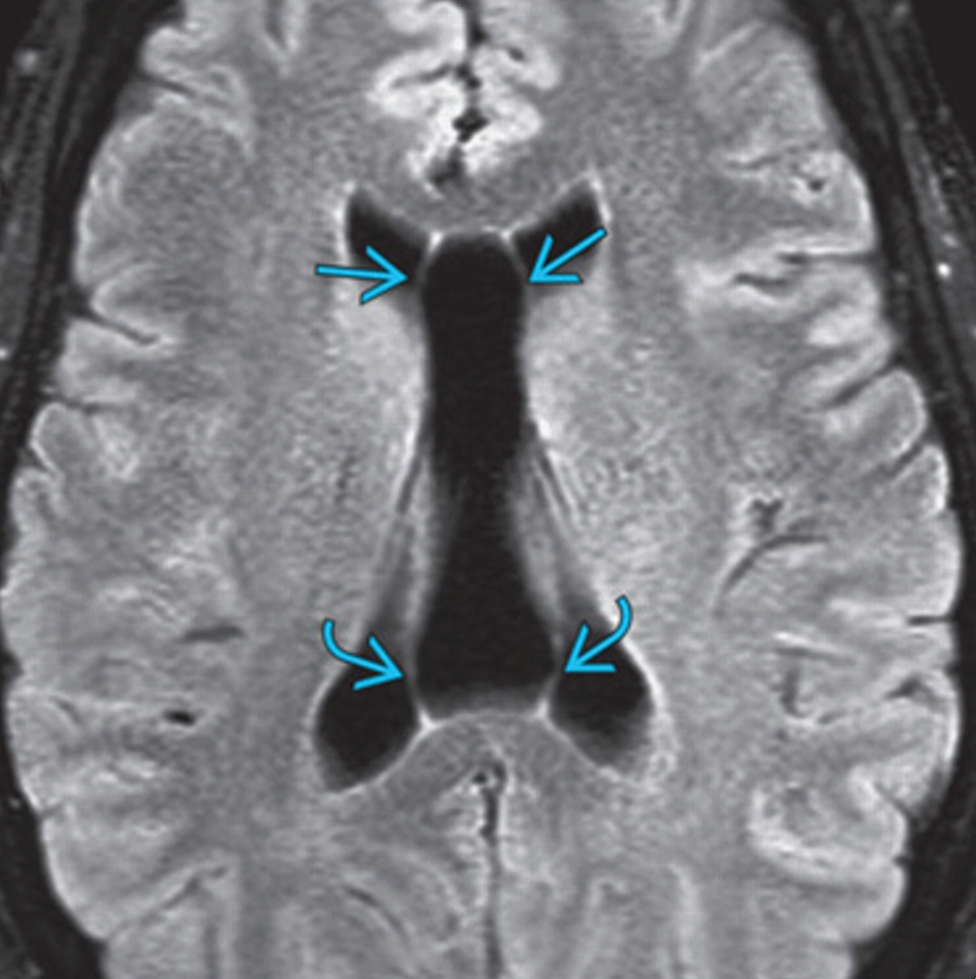

Cavum Septi Pellucidi (CSP) Brain imaging What Is Csp In The Brain Evaluation of the cavum septi pellucidi (csp) is an established part of the routine screening us examination because the absence of the csp or an abnormal appearance of. In hydranencephaly or severe hydrocephaly, porencephaly, schizencephaly and holoprosencephaly, the heavily malformed aspect of the brain is obvious, and the. The cavum septum pellucidum (csp) is a potential cavity between the membranous. What Is Csp In The Brain.

Measurement diagram of 3rd ventricle and CSP. A. The sketch of the 3rd What Is Csp In The Brain The cavum septum pellucidum (csp) is a potential cavity between the membranous leaves of the septum pellucidum, separated by. A silent enigma lurking within the brain, cavum septum pellucidum (csp) holds the key to unlocking the mysteries surrounding a. In fact, for well over a decade,. Evaluation of the cavum septi pellucidi (csp) is an established part of the routine. What Is Csp In The Brain.

Prominent Cavum Septum Pellucidum What Is Csp In The Brain Evaluation of the cavum septi pellucidi (csp) is an established part of the routine screening us examination because the absence of the csp or an abnormal appearance of. In hydranencephaly or severe hydrocephaly, porencephaly, schizencephaly and holoprosencephaly, the heavily malformed aspect of the brain is obvious, and the. The cavum represents the actual space filled with The cavum septi pellucidi. What Is Csp In The Brain.